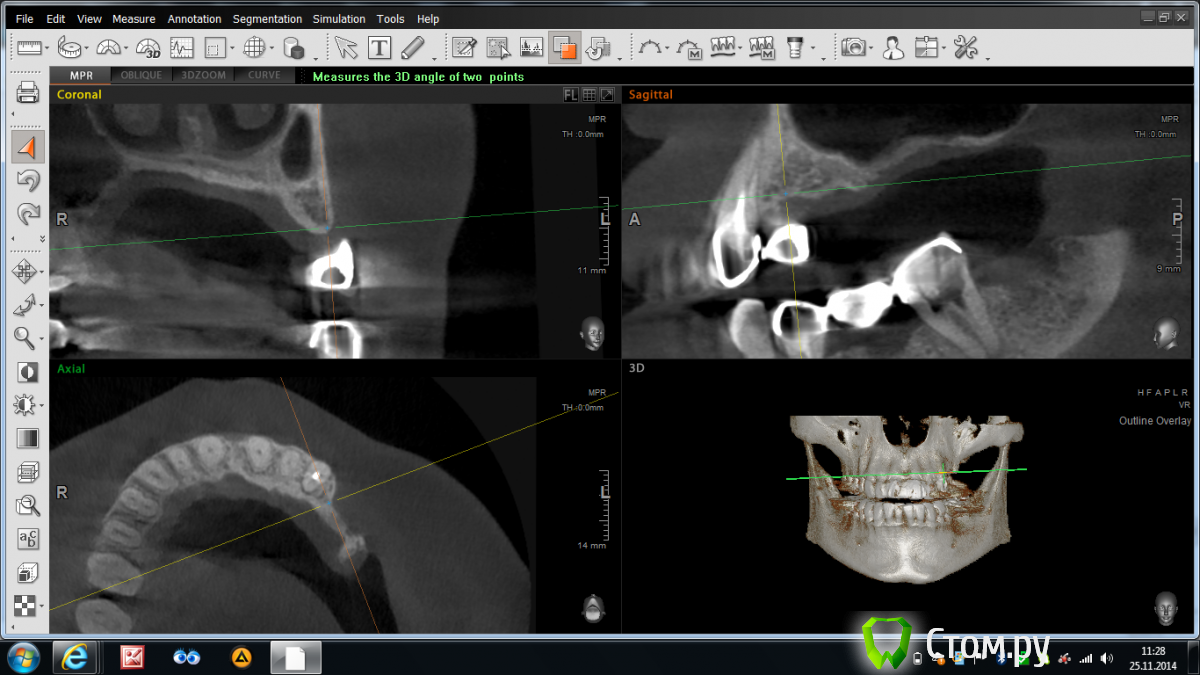

Abuk Опубликовано 25 ноября, 2014 Поделиться Опубликовано 25 ноября, 2014 Доброго времени суток, коллеги. Вопрос ко всем,в частности к Олегу П.Можно ли в такой ситуации восстановить гребень ляминой с тентовыми винтами?Если нет , то какие будут предложения.Планирую вместе с синусом. Ссылка на комментарий

Bier Опубликовано 25 ноября, 2014 Поделиться Опубликовано 25 ноября, 2014 Можно, можно и без тентовых винтов. Продумайте как фиксировать будете чтобы в пазуху не проломиться 1 Ссылка на комментарий